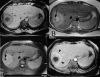

We report a new case of a brucellar liver abscess (brucelloma) in a young woman without previous remote brucellosis who presented with pronounced systemic and mild local symptoms. Brucelloma is the result of calcification of a granoulomatous reaction induced by persistent Brucella in macrophages. It represents a rare manifestation that follows previously undetected brucellosis. We describe the findings in plain radiograph, ultrasound, computed tomography, and magnetic resonance images. Together with the positive serology, imaging yielded important elements supporting the diagnosis. Modern radiological techniques also contributed to the final therapeutic management, preventing unnecessary laparotomy. Sequencing confirmed the definite diagnosis of Brucella melitensis as the causative factor.